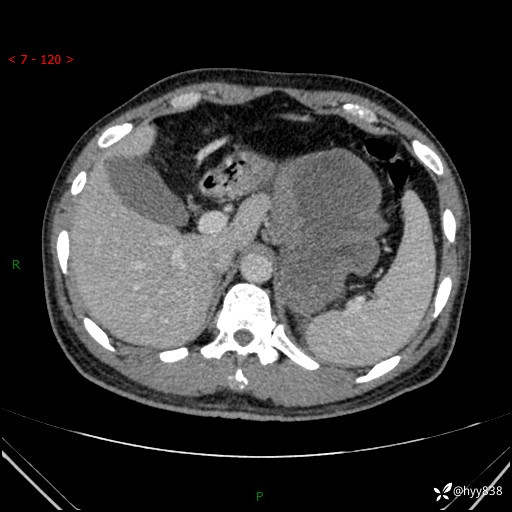

病例39岁/女,左侧腰痛入院。腹腔囊实性肿块,定位、定性---结果公布~

性别:男

年龄:39岁

简要病史:左侧腰痛待查,CT发现腹腔占位

腹部CT平扫+增强